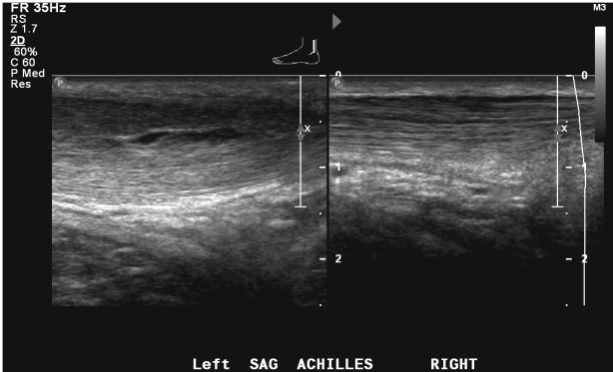

Ultrasonography

We perform MSK ultrasound at the University campus of UMMMC and Marlborough Hospital. A variety of diagnostic, therapeutic and image-guided procedures receive supervision and interpretation by an MSK radiologist. We also provide inpatient diagnostic ultrasound of the extremities at both University and Memorial Hospitals.